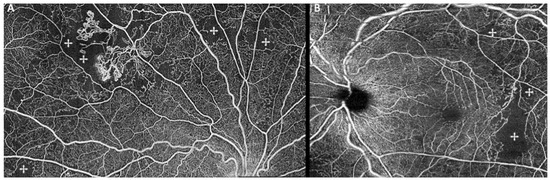

- Vaz-Pereira, S.; Silva, J.J.; Freund, K.B.; Engelbert, M. Optical coherence tomography angiography features of neovascularization in proliferative diabetic retinopathy. Clin. Ophthalmol. 2020, 14, 3351–3362. [Google Scholar] [CrossRef] [PubMed]